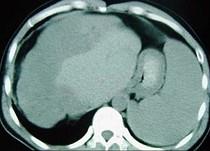

问题 女性,72岁,腹胀不适1年,加重伴恶心、呕吐、乏力1个月,影像检查如图,最可能的诊断为 ( )

选项 A.肝硬化腹水 B.原发性肝癌 C.肝血管瘤 D.巴-希综合征 E.局灶脂肪肝

答案 D